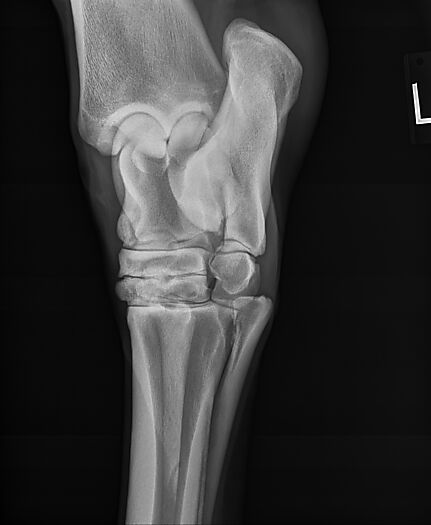

**Tex sells at the Colorado Horse Sale's Best of the West Select Sale on May 30th in Castle Rock, CO - He will complete the riding & handling Sift Exam, baseline veterinary exam, and will sell with 4 total radiographs (DLPMO & Front Foot Lateral)**